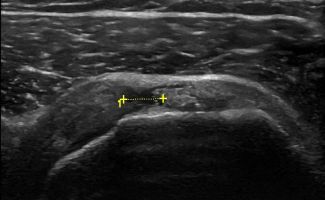

Το Υπερηχογράφημα Ώμου επιτρέπει τον εντοπισμό παθήσεων στους τένοντες του στροφικού πετάλου, όπως:

- Ασβεστοποιός Τενοντίτιδα

- Ρήξη των τενόντων (υποπλάτιος, υπερακάνθιος, υπακάνθιος και ελάσσων στρόγγυλος τένοντας)

Επιπλέον, το Υπερηχογράφημα Ώμου μπορεί να διαγνώσει τενοντοπάθεια, τενοντοελυτρίτιδα ή ρήξη στον τένοντα της μακράς κεφαλής δικέφαλου βραχιονίου.